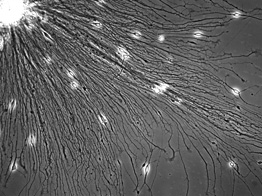

We recognize a need for the development of a novel advance modeling system for in vitro experimentation to bridge the gap between AMD, DR research in animal models and its utility in human patient population. We propose tissue samples taken from patients can be used to create three-dimensional cell culture models. We propose such models can identify molecular mechanisms, as well as discover potential biomarkers and specific therapeutic targets.